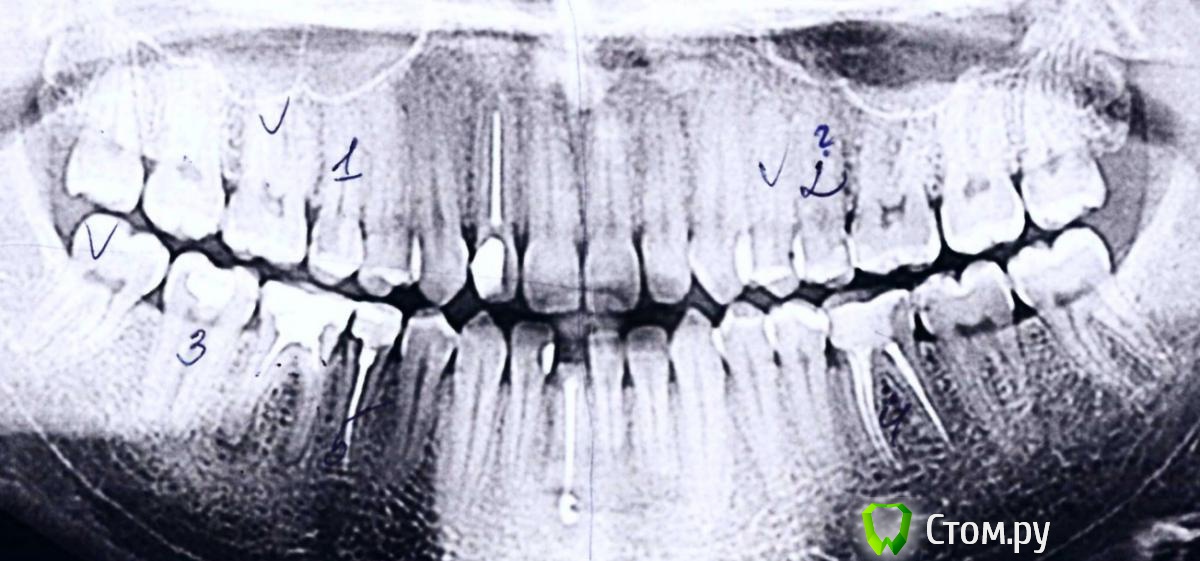

Ситуация: Откололся 41 зуб, в котором был в 2002 залечен пульпит. Остался только корень. Вяснилось, что под корнем есть киста.  Ортопед сказал, что можно либо залечить кисту и поставить культевую вкладку с коронкой, либо выдернуть зуб и поставить имплант с коронкой. Остановились на варианте с лечением. На рентгене уже состояние после лечения этого зуба. И терапевт и ортопеды говорят, что можно уже начинать ставить культевую вкладку. У меня осталось пара вопросов.

post-38002-0-44745200-1394548673_thumb.jpeg